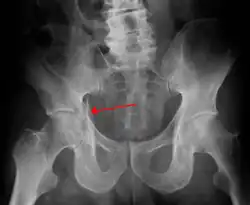

Fractures of the acetabulum occur when the head of the femur is driven into the pelvis. This injury is caused by a blow to either the side or front of the knee and often occurs as a dashboard injury accompanied by a fracture of the femur.[1]

| Posterior wall | This is the most common variety of acetabular fracture. It typically occurs due to dashboard injury; when a person travelling in a vehicle involved in a head-on collision, the force applied over the flexed knee travels along the femur bone to the head of the femur, breaking the posterior wall of the acetabulum. The head of the femur is dislocated outside the joint. | T shape | When a transverse fracture also had a vertical fracture line, it is called a T shape fracture. Here the innominate bone is broken in such a way that all three parts of it, the ilium, the ischium and the pubis are separated from one another. This is a three part fracture. Though both columns are broken, the weight bearing dome is still attached to the main part of the ilium and hence it is not a true fracture of both columns.